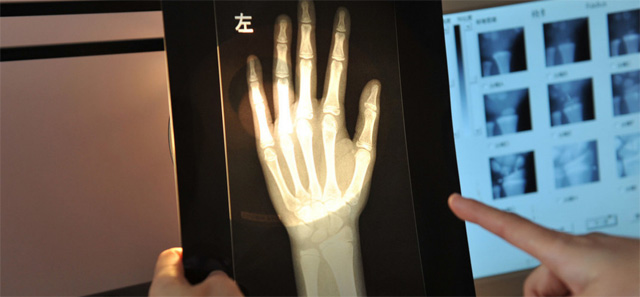

這個(gè)輻射到底對(duì)兒童有沒影響呢?其實(shí)影響不大的,預(yù)測(cè)孩子的骨齡是對(duì)身高的評(píng)估。怎樣監(jiān)測(cè),兒童在正常生長(zhǎng)發(fā)育的過程中,隨著年齡的增加。骨骼線會(huì)逐漸的鈣化直至完全骨化,骨骼線閉合。骨齡是各個(gè)年齡骨的成熟度,正常情況下骨骼的年齡,和實(shí)際的年齡不應(yīng)相差正負(fù)超過一歲。提前或者落后太多都是不正常的。用兒童的左手腕拍一張DR片來測(cè)骨齡,通過影像來觀測(cè)兒童骨骼生長(zhǎng)發(fā)育情況。預(yù)測(cè)兒童的生長(zhǎng)發(fā)育潛力。這個(gè)骨齡監(jiān)測(cè)是比較準(zhǔn)確的。

還有精準(zhǔn)骨骼線檢查的位置在膝關(guān)節(jié),通過DR拍片可以明確的看到骨骺線的狀態(tài)。這就是為什么檢查了手掌的骨骼線還有檢查膝關(guān)節(jié)的。手掌的骨骼線閉合了,也不一定代表不能生長(zhǎng)了,通過精準(zhǔn)的骨骼線檢查,判斷兒童是否有長(zhǎng)高的可能。膝關(guān)節(jié)骨骼線未閉合就可以進(jìn)行身高的干預(yù)治療。